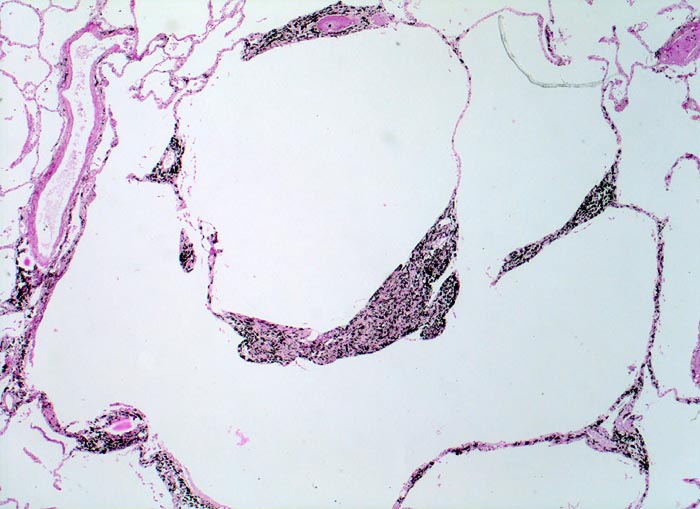

Morphologisch lassen sich zentroazinäre (> 3484), panazinäre (> 3599) und paraseptale Emphyseme (> 3487) unterscheiden sowie das Narbenemphysem in der Umgebung vernarbter Lungenareale. Das zentroazinäre (=zentrolobuläre) Emphysem (vorliegendes Präparat) beginnt primär in den respiratorischen Bronchiolen und breitet sich von dort nach peripher aus. Es spart die terminalen Bronchiolen aus. Diese Form des Emphysems ist assoziiert mit langdauerndem Zigarettenrauchen und befällt bevorzugt die Lungenoberlappen.

Histologisch sind die Lufträume erweitert und enthalten frei flottierende Alveolarsepten mit knotenförmigen Spitzen. Peribronchiolär finden sich beim zentroazinären Emphysem reichlich Ablagerungen von schwarzem Anthrakosepigment.

• Schwarz pigmentierte erweiterte Azinuszentren.

• Fragmentierte Alveolarsepten im Bereich der erweiterten Azinuszentren.

• Bruchstücke von Alveolarsepten und Gefässen im Zentrum der emphysematischen Räume. Das sollte der Kliniker dem Pathologen mitteilen: